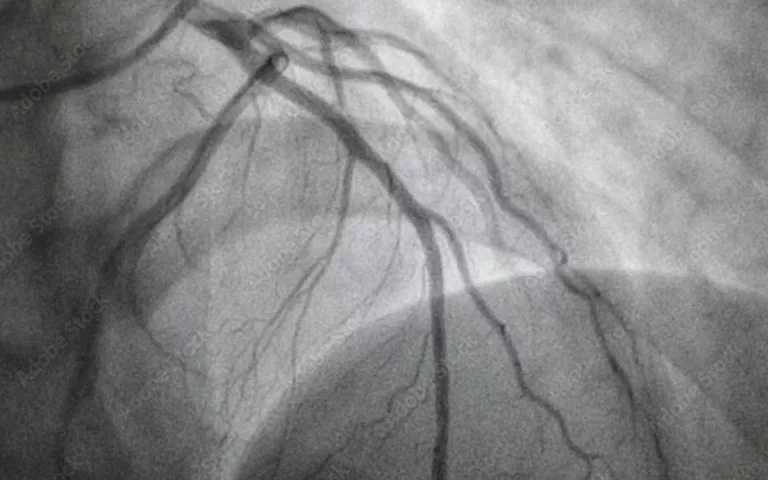

Atherosclerosis is the build-up of cholesterol plaques inside blood vessels that cause heart attacks.